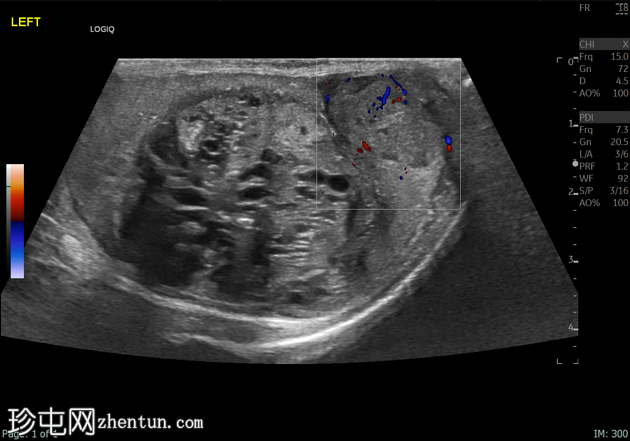

3.png

左侧睾丸肿大,体积约56 mL,可见弥漫性微结石,以及三个内部等回声病灶,伴囊性变、微钙化和明显血流信号,最大病灶大小约4.8 x 3.2 cm。